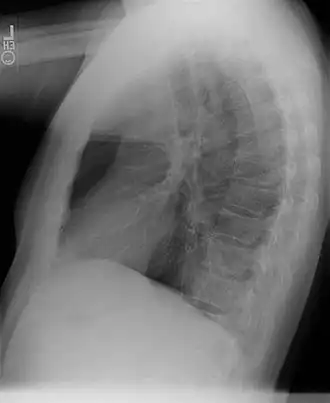

Un secuestro broncopulmonar es una anormalidad congénita de una porción del pulmón que está separada del resto del parénquima pulmonar, recibiendo su aporte sanguíneo de una arteria sistémica.

Generalmente diagnosticada en niños. El tratamiento es la segmentectomía a través de una toracotomía. Son más frecuente en el pulmón izquierdo y en los lóbulos inferiores (60%-90%), aunque pueden verse en cualquier lóbulo, incluir todo el pulmón o incluso debajo del diafragma simulando un tumor abdominal.